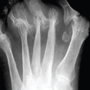

Caso 2: Hallux Valgus del Adulto

Haga click para agrandar las imágenes